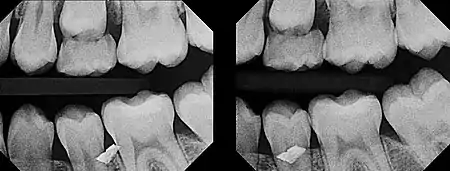

In 1909, Charles A. Clark described a radiographic procedure for localizing impacted teeth to determining their relative antero-posterior position.[1] If the two teeth (or, by extension, any two objects, such as a tooth and a foreign object) are located in front of one another relative to the x-ray beam, they will appear superimposed on one another on a dental radiograph, but it will be impossible to know which one is in front of the other. To determine which is in front and which is behind, Clark proposed his SLOB rule, as a complicated set of three radiographs, but which can be simplified as follows using just two:

- Expose another film while angle of the x-ray beam has been changed. If an object moves in the same direction as the source of the x-ray beam, it is lingual to the other object. If the object moves in the opposite direction of the source, it is buccal to the other object.

- Same Lingual; Opposite Buccal

In 1952, Richards amended this rule using only 2 radiographs,[2][3] asserting that the object positioned more buccally will move more relative to the object positioned more palatally or lingually.

As a generalization, but not specifically stated as part of Richards' buccal object rule, the more buccal an object is (i.e. the closer it is to the x-ray source) the more it will move in the second radiograph when repositioning the x-ray source.